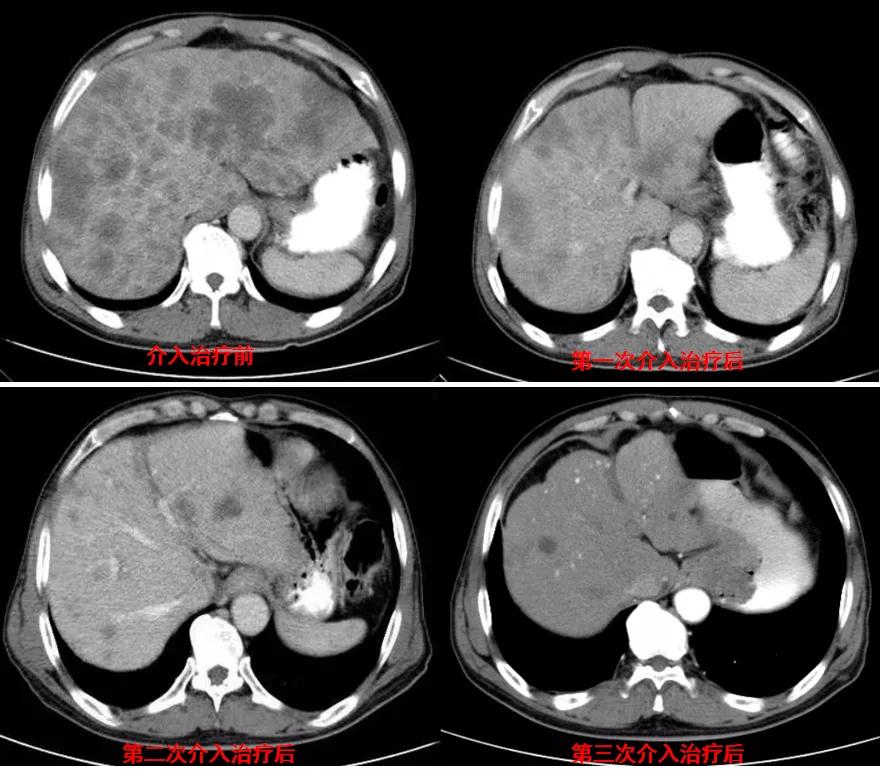

诊治经过:2020年11月25日患者行经皮动脉化疗灌注栓塞术(铂类+氟尿嘧啶);2020年11月30日免疫组化及基因检测结果为:ERBB-2扩增(9倍),VEGFR未突变,MSI微卫星低度不稳定,错配修复蛋白部分缺失(dMMR),MSH2(+弱),MLH1(-),MSH6(+),PMS2(-),CDX2(-),Villin(+),CK8/18(+),Ki67(5%+),CD56(-),Syn(-),CgA(-);患者为HER2阳性,患者肝脏病灶很多,残余正常肝脏体积小,需要寻找对肝功能影响小且抗瘤效果明显的治疗,因此联合吡咯替尼进行系统治疗。2020年12月14日复查结果提示肝脏病灶明显缩小(PR)。结果见图2。

图2

讨论:2020年12月14日患者复查示原发灶稳定,肝转移灶明显缩小,达到PR。患者一般状况好(ECOG:0分),治疗疗效显著,转移病灶多发且MSI微卫星不稳定为低度不稳定,因此不建议行外科手术及免疫治疗,继续行当前介入联合靶向治疗。